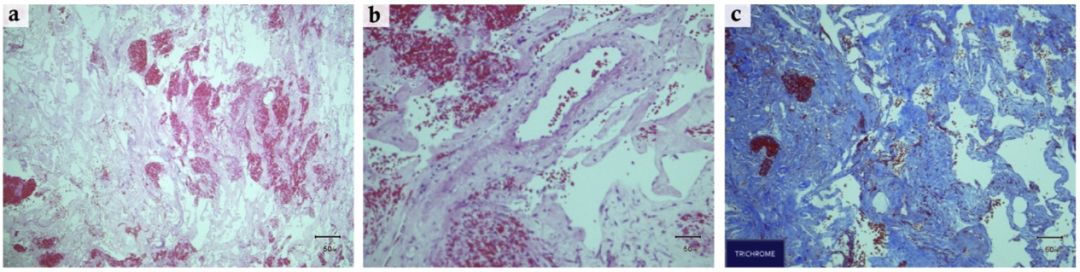

常规病理结果:鞍区胶原纤维囊壁样组织,局部间淋巴浆细胞浸润,未见内衬上皮,并见大量嗜伊红色变性坏死组织,无定形,伴胆固醇结晶,呈黄色肉芽肿样改变。免疫组化结果:EMA-,Vimentin部分+,PR-,S-100-,P53-,Ki67-,SMA-,Desmin-(图6)。

图6. A:H&E染色10X;B:H&E染色 20X 可见并见大量嗜伊红色变性坏死组织

UCLA病理会诊:见纤维组织,伴坏死细胞及丰富的陈旧性血肿,包括纤维素、胆固醇裂隙、巨细胞反应、含铁血黄素巨噬细胞和其他单核炎性细胞。建议需鉴别诊断的疾病为:垂体腺瘤卒中、坏死性/出血性颅咽管瘤、黄色肉芽肿和其他坏死性病变。